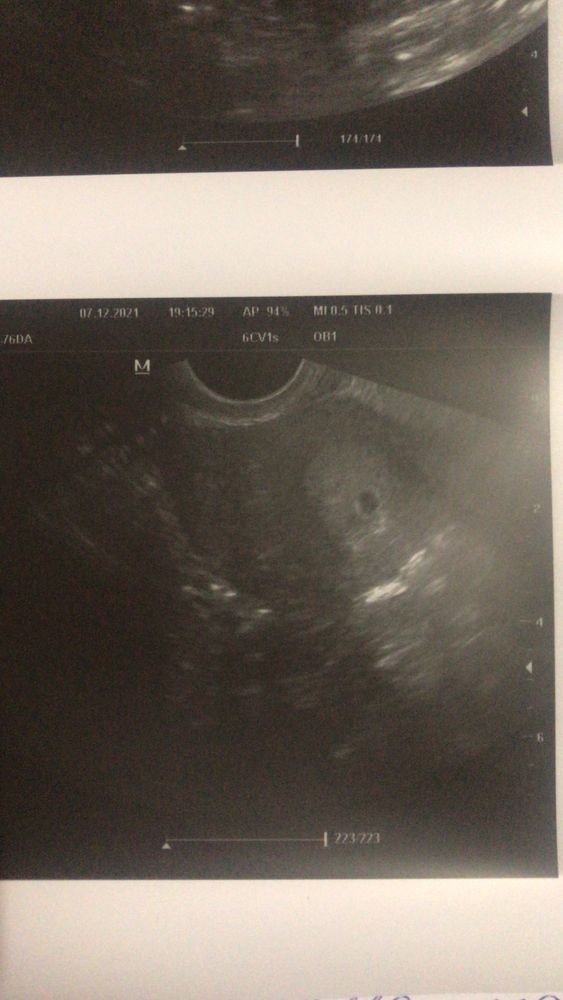

Узи 4 дня задержки

Узи 4 дня задержки 147 фото